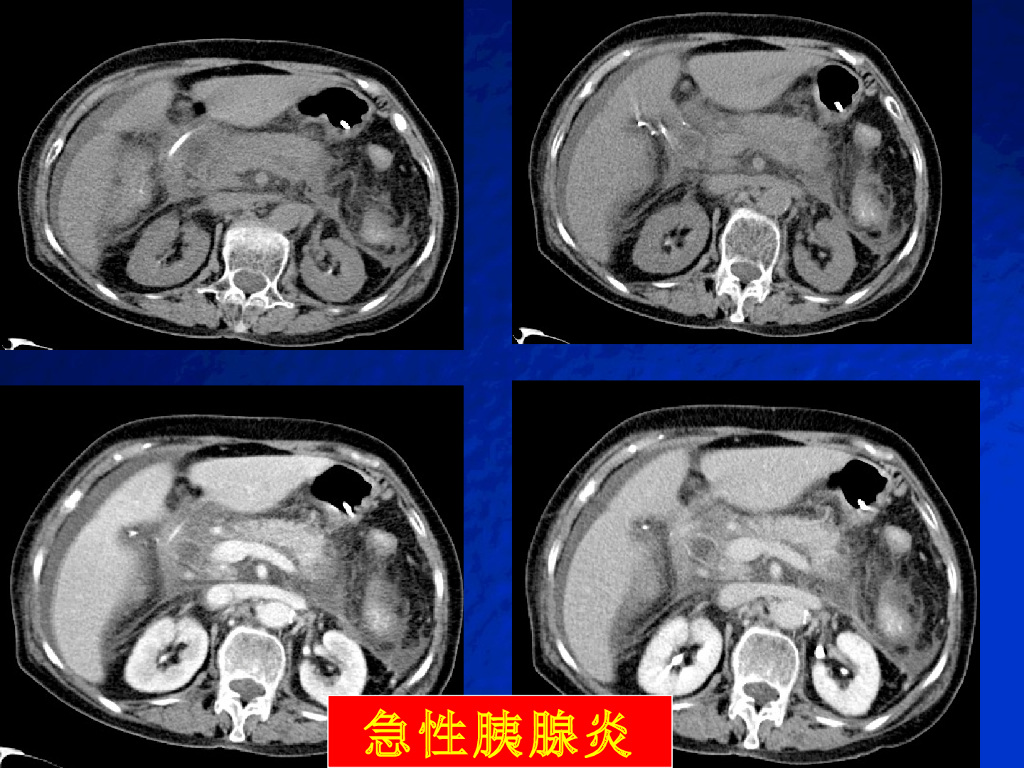

《放射诊断学》演示文稿-胰腺病变实习.pdf